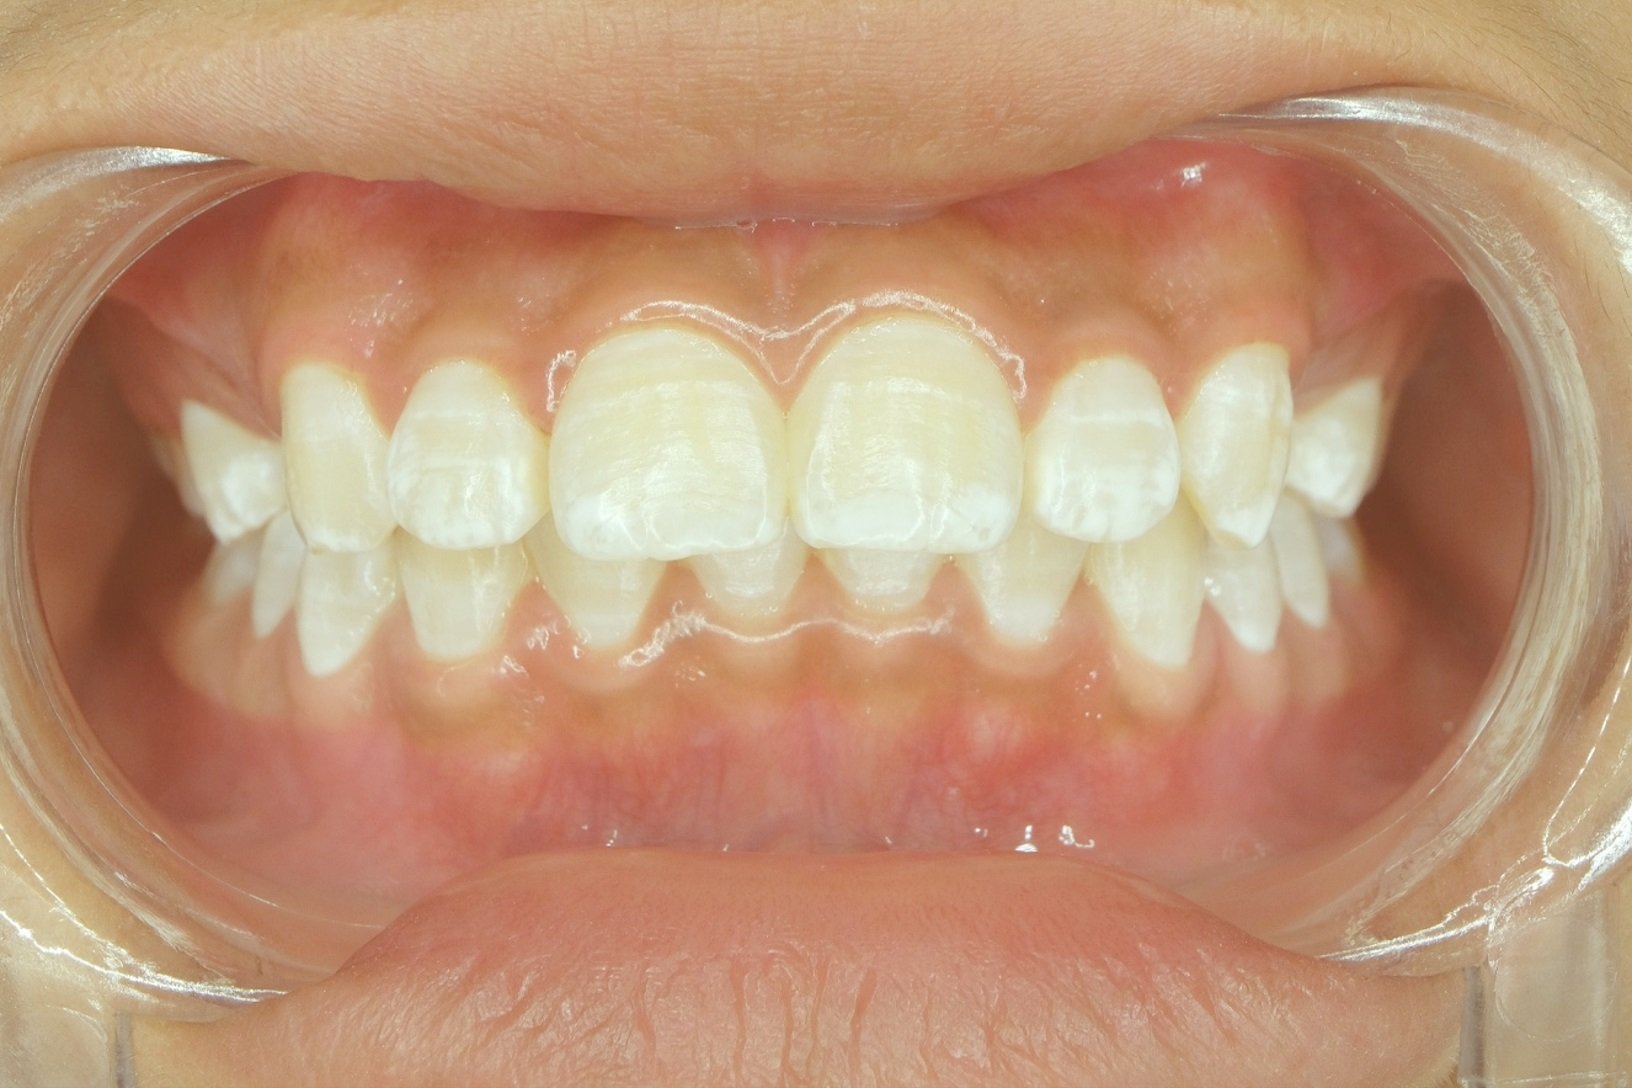

White dots on gums can be caused by a variety of factors, including canker sores, oral thrush, or even oral cancer. Canker sores are small, painful ulcers that can develop on the gums and other areas of the mouth. Oral thrush is a fungal infection that can also cause white patches on the gums. In more severe cases, white dots on gums can be a symptom of oral cancer, which requires immediate medical attention.

Additionally, poor oral hygiene, smoking, or certain medications can also contribute to the development of white dots on the gums. It is important to consult with a dentist or healthcare provider to determine the underlying cause of the white spots and to determine the appropriate treatment plan.